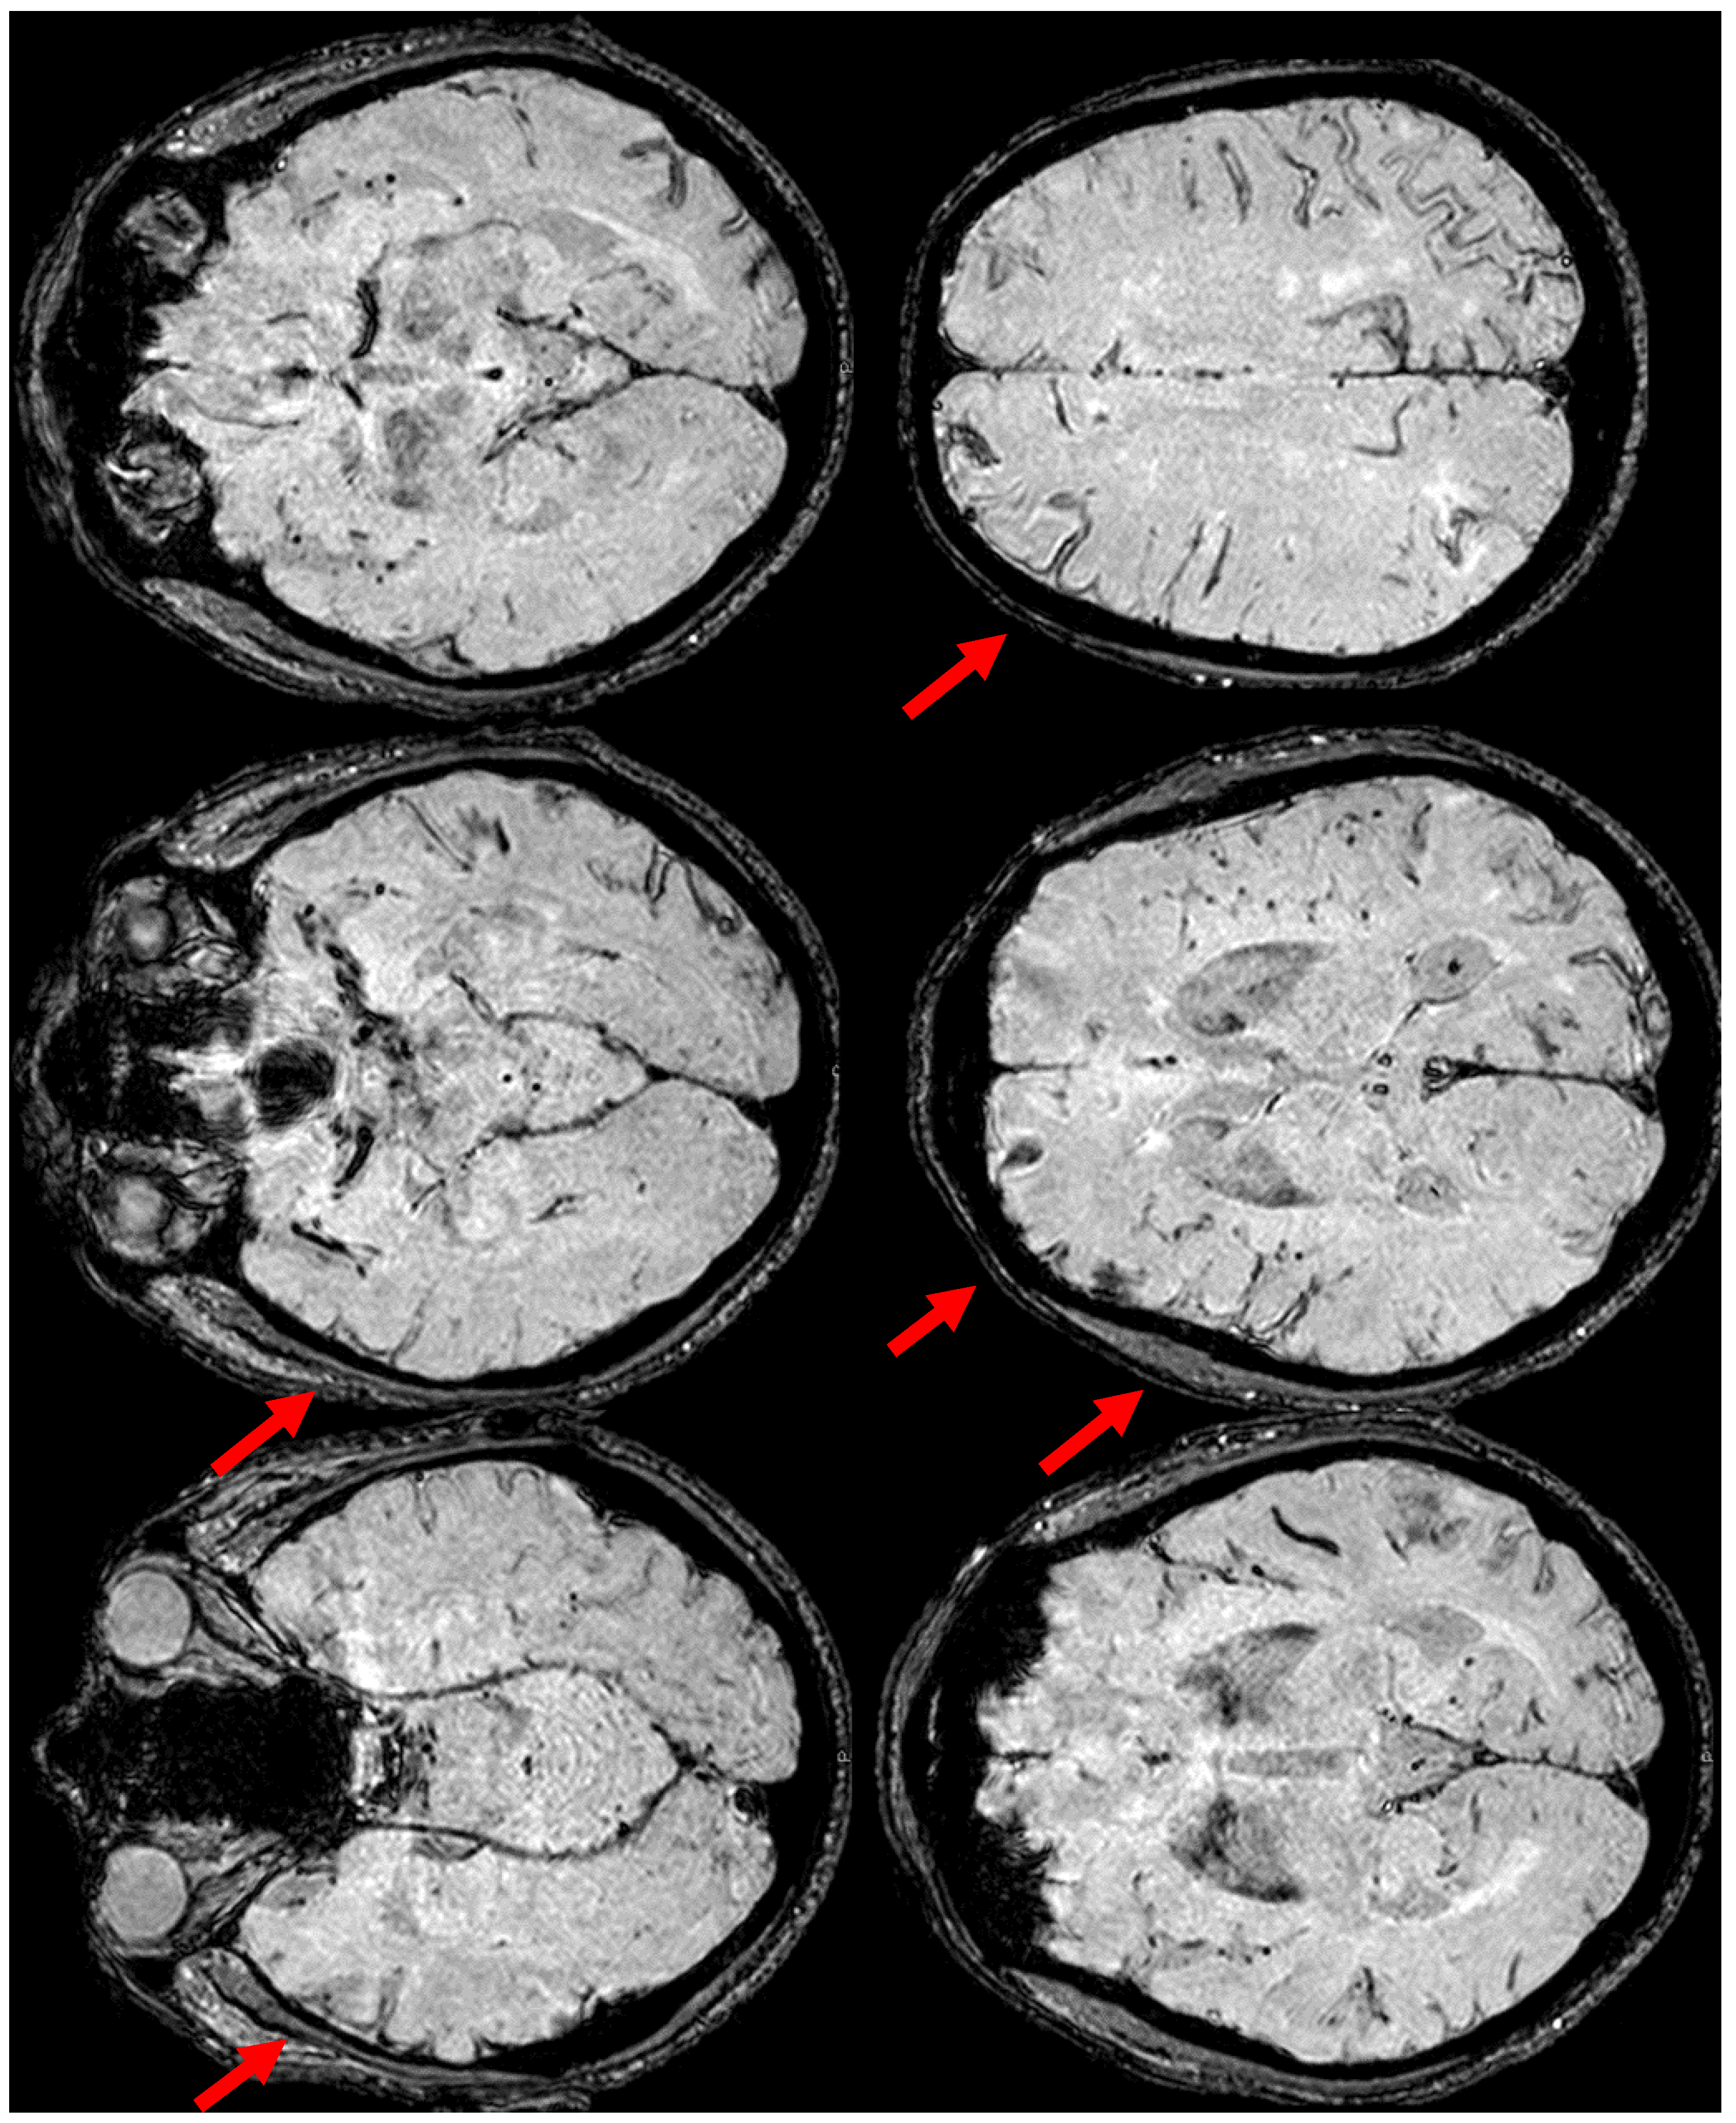

7. April 2018: Second Recurrent CAA-Related Inflammation

8. April 2018: Third Recurrent CAA-Related Inflammation